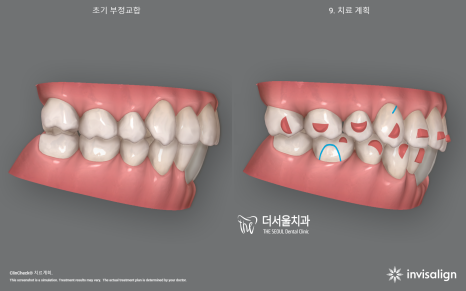

2. 인비절라인 시뮬레이션

시뮬레이션을 영상으로 보니 신기하죠?

인비절라인 클린첵 시뮬레이션을 하면

이렇게 치료 전, 후 를 나눠서 어떤식으로

치아들이 이동이 되면서 빈 틈이 만들어지며

다시 그 빈틈을 메꾸려 다른 치아들을

이동시켜줘야 되는지 술자에게

많은 정보들을 제공합니다.

물론, A.I 기반이라서 최종 수정은

담당 주치의가 직접 진행을 해야 되죠.

이 환자의 경우 임플란트 시술을

해야 되는 상황이라서 우선 임플란트를

심을 수 있는 환경부터 조성해야 됩니다.

이런 것 또한 미리 시뮬레이션에

데이터를 집어넣어서 임플란트의

예상 위치에 따른 교정치료의 종점을

예상할 수 있습니다.